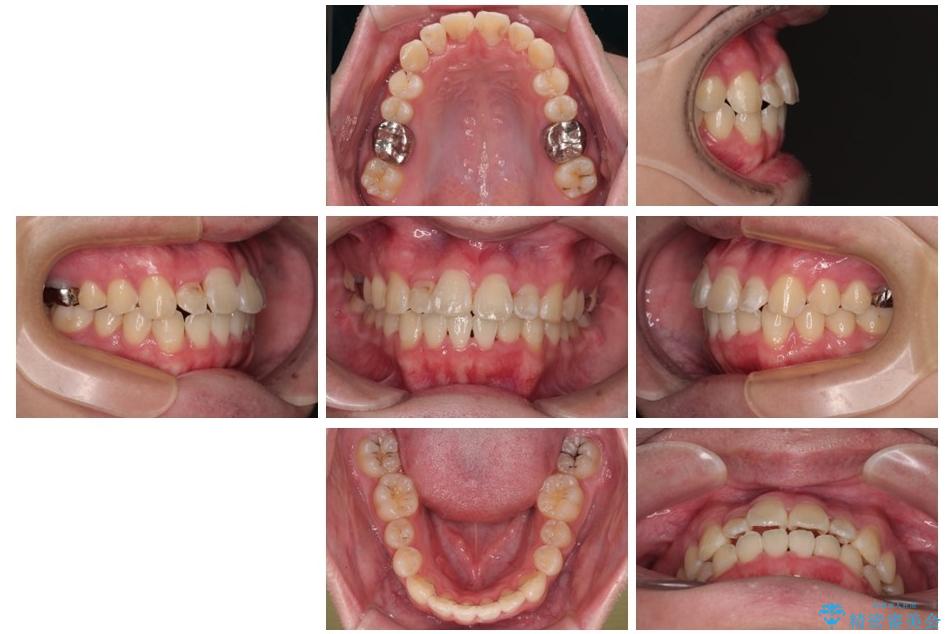

「歯並びがデコボコしていて、上下の中心がズレているのが気になる…」という悩みで来院された患者さまの症例をご紹介します。

初診時の状態

・上下ともに歯がきれいに並びきらず、がたつきが見られました。

・上下の前歯の中心(正中)がずれています。

・特に上顎の幅が狭いため、下顎の歯列も内側に入り込み、歯が並ぶスペースが不足していました。

治療方針

このような歯列の狭さに起因するデコボコを改善するために、**MARPE(骨に固定する上顎急速拡大装置)**を使用して、上顎の横幅を拡大し、これにより歯が並ぶためのスペースを確保し、メタルブラケットを用いて歯列を整えていく計画としました。

治療前

治療後

• 1年でここまで変わる!歯列のがたつきと正中のズレを改善した矯正治療(メタルブラケット×MARPE) 治療後画像